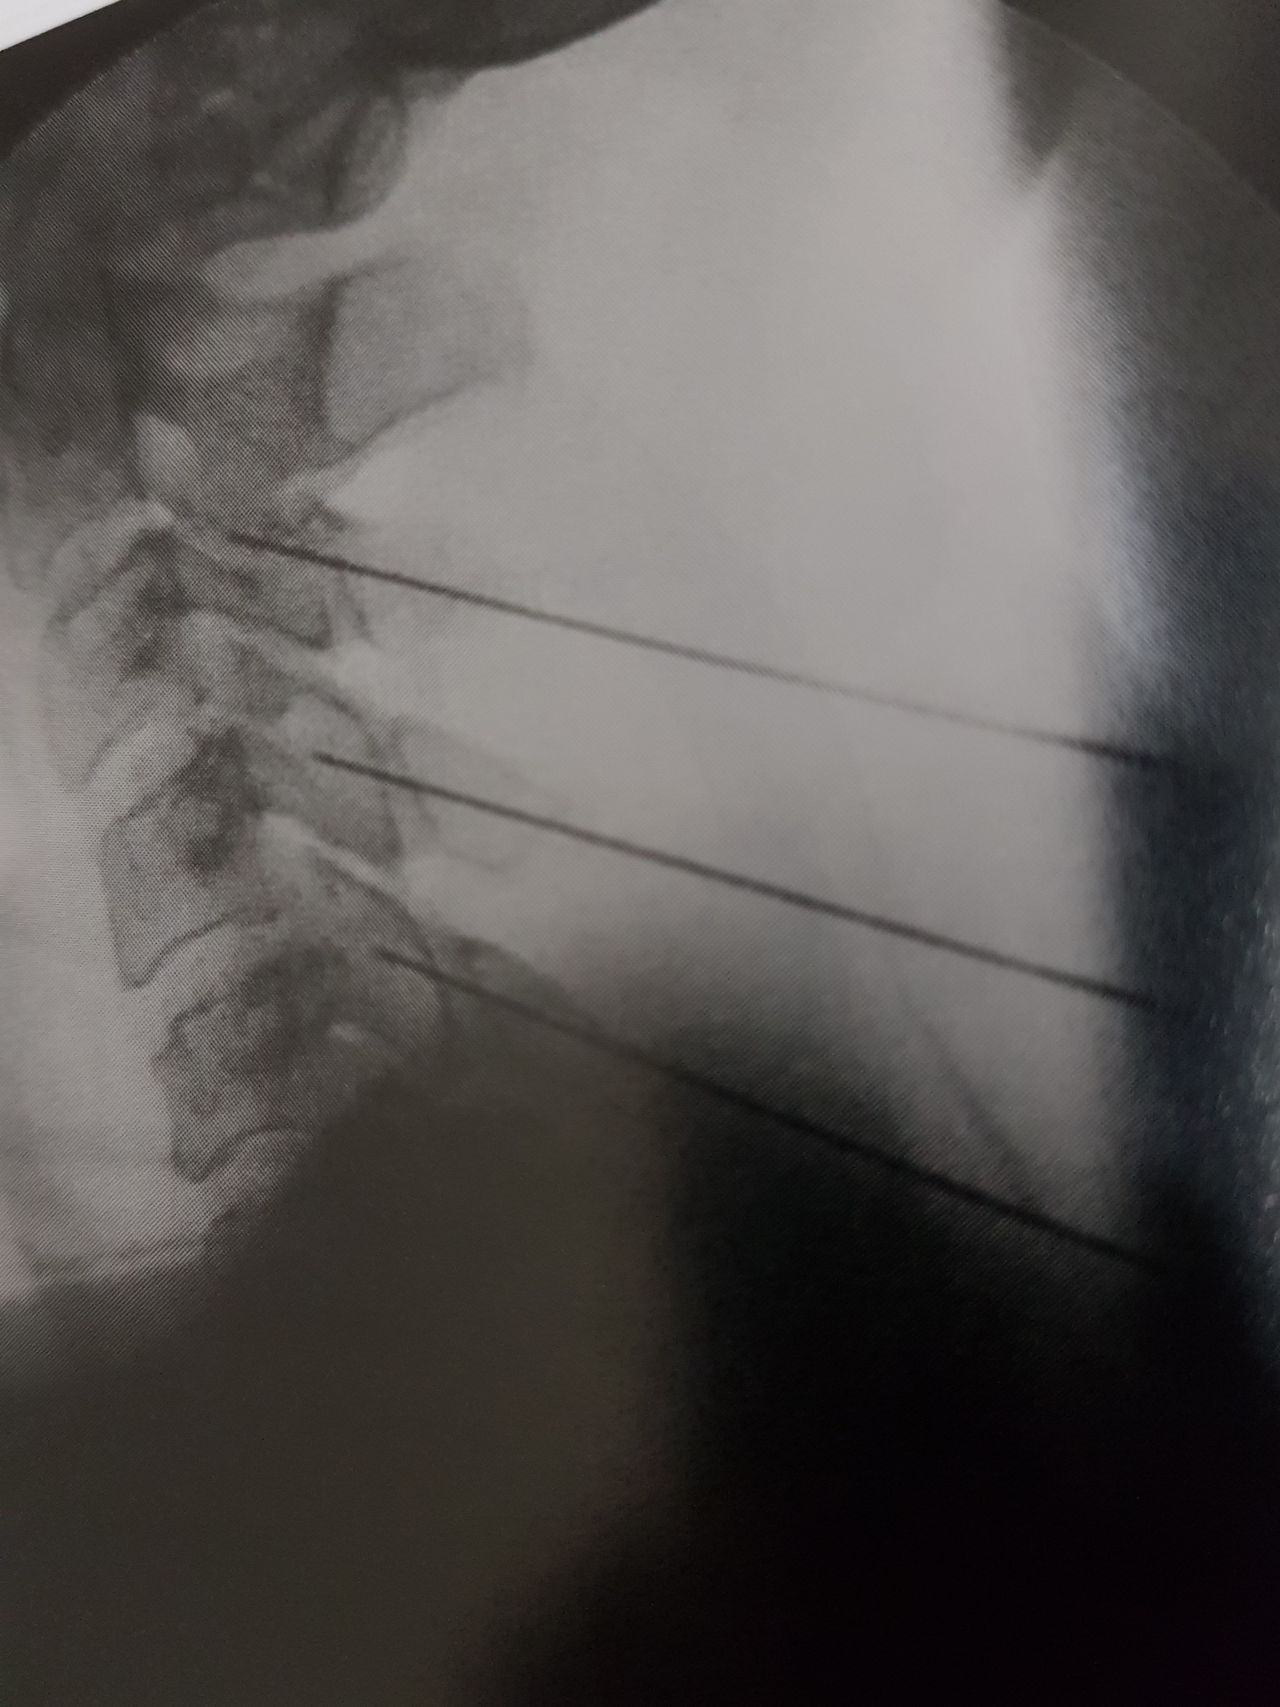

3. Procedimiento guiados a los sitios dolorosos o a estructuras nerviosas para inhibir o bloquear el dolor, conde alivió seguridad y bajo condiciones orientadas con fluroscopia (Rxs) y por medio de ultrasonido, y de vanguardia con radiofrecuencia pulsada que extienda el tiempo de semanas a años